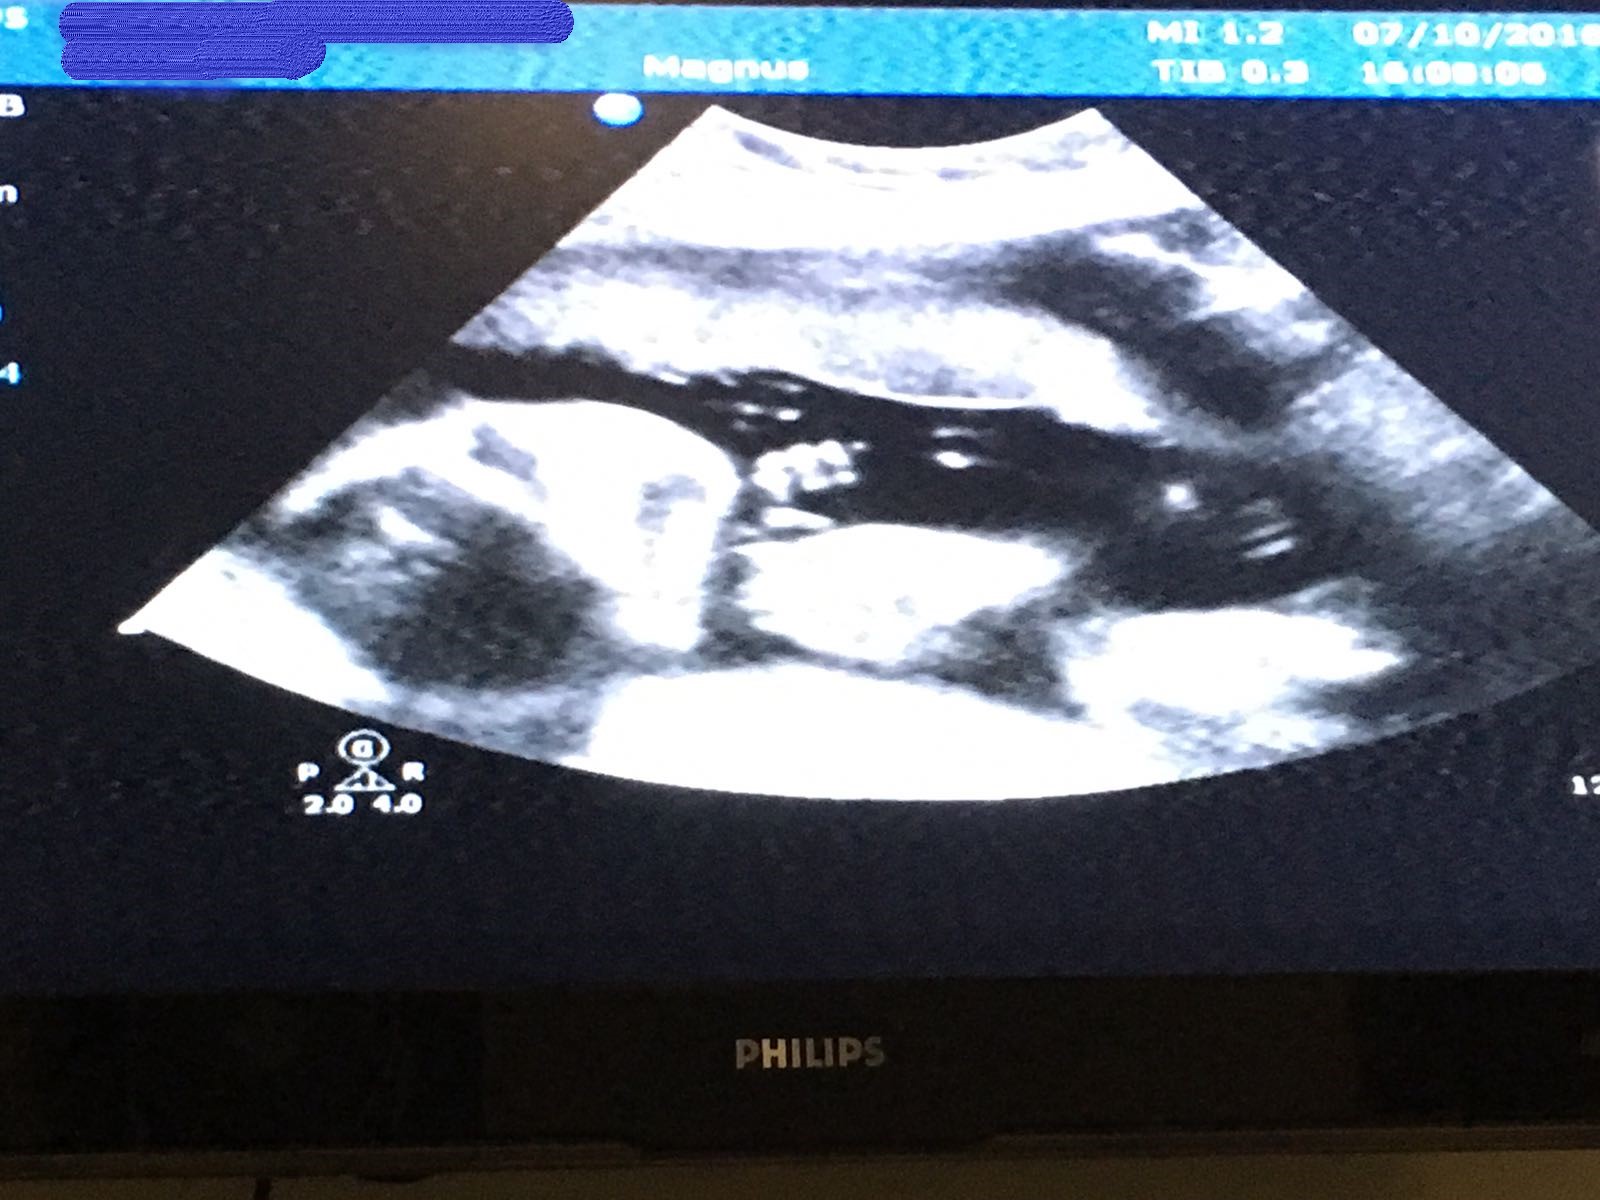

可幸的是之後幾次再做檢查,都發現丸B的腦室有變細,更加所有生長都正常,回想起嚟真係唔容易,特別係抽羊水呢個經歷,記得嗰朝去到醫院真係好驚,好彩老公可以陪住我抽,而醫生都真係非常細心,照住超聲波睇住BB嘅位置,如果唔係成支針拮入去肚入面都真係幾驚呀!

結果入醫院又搞咗幾個鐘,開始聽BB心跳聲、抽血、超聲波等,而我內心非常之焦急,因為當時我記得夜晚係要食團年飯嘅,好彩醫生肯放我返屋企渡假,第二朝先再返去,又要再飲多杯糖水。好彩最後檢查所有嘢正常,飲完糖水就可以返屋企待產啦!